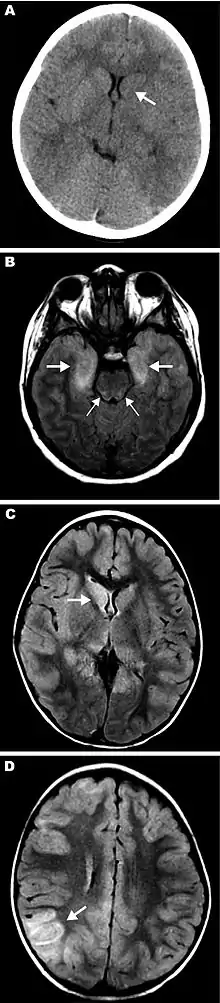

Eastern equine encephalitis (EEE), commonly called Triple E or sleeping sickness (not to be confused with African trypanosomiasis), is a disease caused by a zoonotic mosquito-vectored Togavirus that is present in North, Central, and South America, and the Caribbean. EEE was first recognized in Massachusetts, United States, in 1831, when 75 horses died mysteriously of viral encephalitis. Epizootics in horses have continued to occur regularly in the United States. It can also be identified in donkeys and zebras. Due to the rarity of the disease, its occurrence can cause economic impact beyond the cost of horses and poultry.[2] EEE is found today in the eastern part of the United States and is often associated with coastal plains. It can most commonly be found in East Coast and Gulf Coast states.[1] In Florida, about one to two human cases are reported a year, although over 60 cases of equine encephalitis are reported. In years in which conditions are favorable for the disease, the number of equine cases is over 200.[3] Diagnosing equine encephalitis is challenging because many of the symptoms are shared with other illnesses and patients can be asymptomatic. Confirmations may require a sample of cerebral spinal fluid or brain tissue, although CT scans and MRI scans are used to detect encephalitis. This could be an indication that the need to test for EEE is necessary. If a biopsy of the cerebral spinal fluid is taken, it is sent to a specialized laboratory for testing.[4]